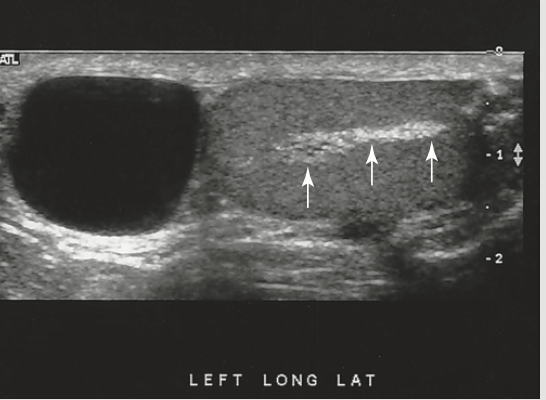

what are the arrows point to

haustra